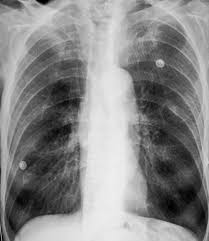

Chest x ray hyperinflation definition. Narrowing of the transverse cardiac diameter felson s principles of chest roentgenology by lawrence goodman states that when the right hemidiaphragm lies below the 10th posterior rib it is diagnosed as hyperinflation. Chest x ray definition a chest x ray is a procedure used to evaluate organs and structures within the chest for symptoms of disease. Airways difficult to see hyperinflation bilateral 9 posterior ribs reduced vascular markings flat diaphragms small heart unilateral 9 posterior ribs reduced vascular markings flat hemi diaphragm herniation of lung. In some cases however the lungs may appear hyperinflated on a chest x ray for reasons that have nothing to do with lung function.

It happens when you can t exhale or push out all of the air that s in your lungs the air gets trapped and takes up. If it isn t clear what s causing the hyperinflation your doctor might recommend additional testing such as a computerized tomography ct of the chest and pulmonary function tests. Increases heart size 3. Hyperinflated lungs are present in many chronic chest conditions in particular copd and asthma.

A chest x ray is the most common tool used to diagnose hyperinflation of the lungs. Chest x rays include views of the lungs heart small portions of the gastrointestinal tract thyroid gland and the bones of the chest area. Small lung volumes 2. More than 6 anterior or 10 p.

In some cases lungs can appear hyperinflated on x rays for reasons unrelated to lung function. Enlargement of retrosternal space on lateral chest x ray 5. The radiologist will likely take images both during inspiration and expiration. Lung hyperinflation is a common feature of patients with chronic obstructive pulmonary disease copd it is also linked to aging and other chronic diseases that cause airflow obstruction.

X rays are a form of radiation that can penetrate the body and produce an image. This may be evidenced by. Hyperlucent lungs less bronchovascular markings per cm2 c. Often however the condition is detected incidentally meaning that lung hyperinflation was noticed on an imaging test done for another reason.